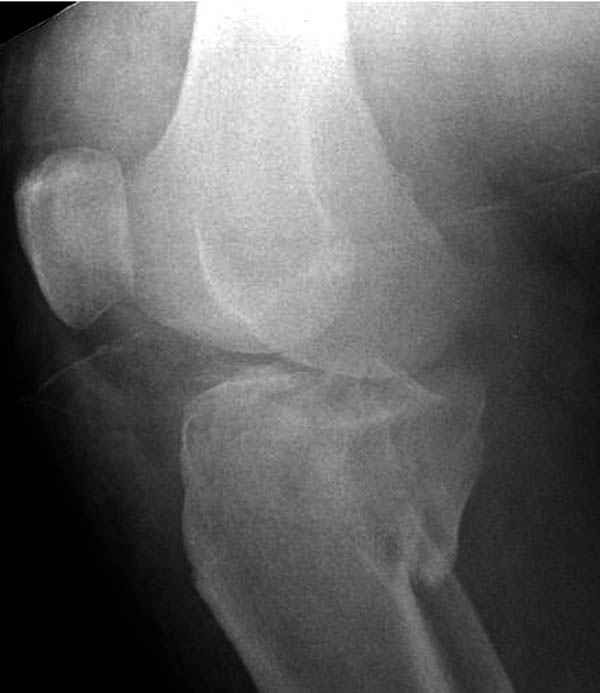

На представленных предоперационных срезах КТ огромный задне-медиальный фрагмент расположен больше кзади, чем медиально. Для планирования, кроме поперечных срезов, надо ориентироваться на корональные срезы, которые укажут топографию верхушки медиального фрагмента.

Доступ к медиальной стороне задний или медиальный, через pes или в пространстве между medial gastroc мышцы.

Надеюсь, представленные снимки разных случаев помогут разобраться в тактике, и критика примется без личной обиды.